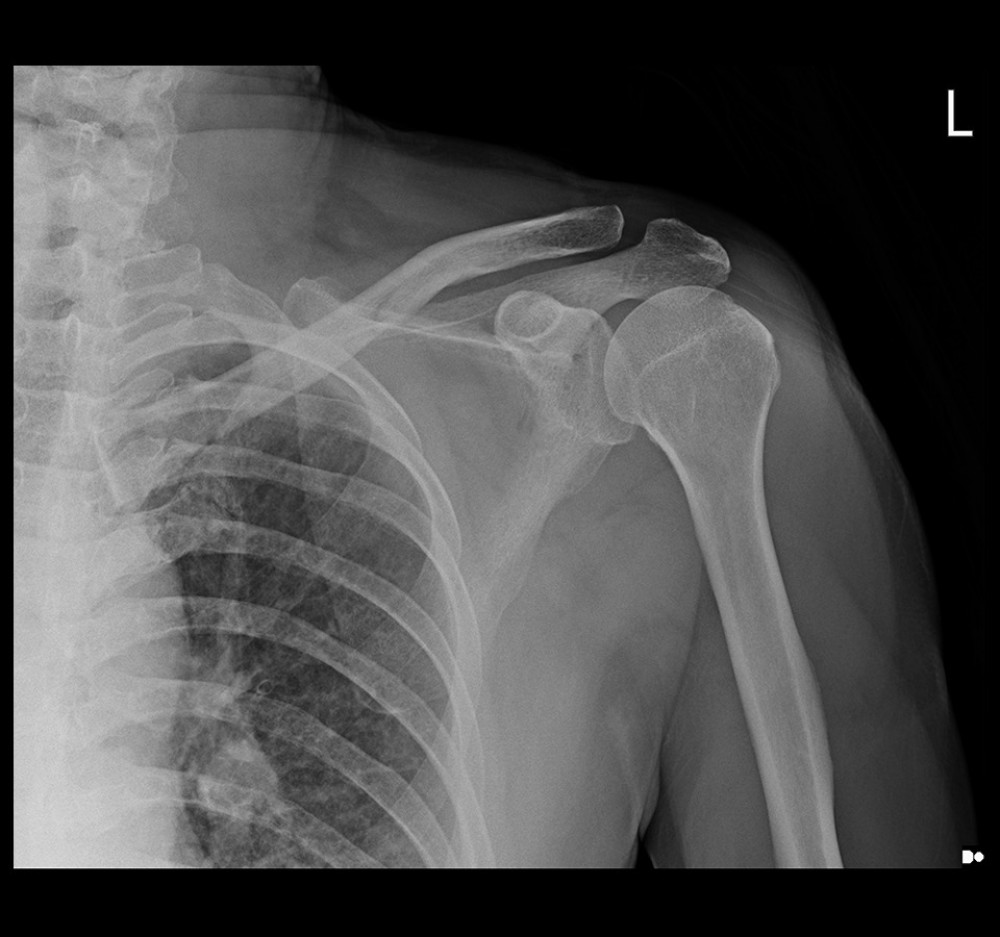

(a) Left closed comminuted midshaft clavicle fracture; (b) fracture end Midshaft Clavicle Fracture Protocol This can happen during a fall onto the shoulder or a car collision. Midshaft clavicle fractures are common traumatic injuries caused by a direct impact to the shoulder girdle and is most commonly seen in young, active adults. Clavicle fractures are often caused by a direct blow to the shoulder. Operative treatment of displaced midshaft clavicle fractures in adult patients. Midshaft Clavicle Fracture Protocol.